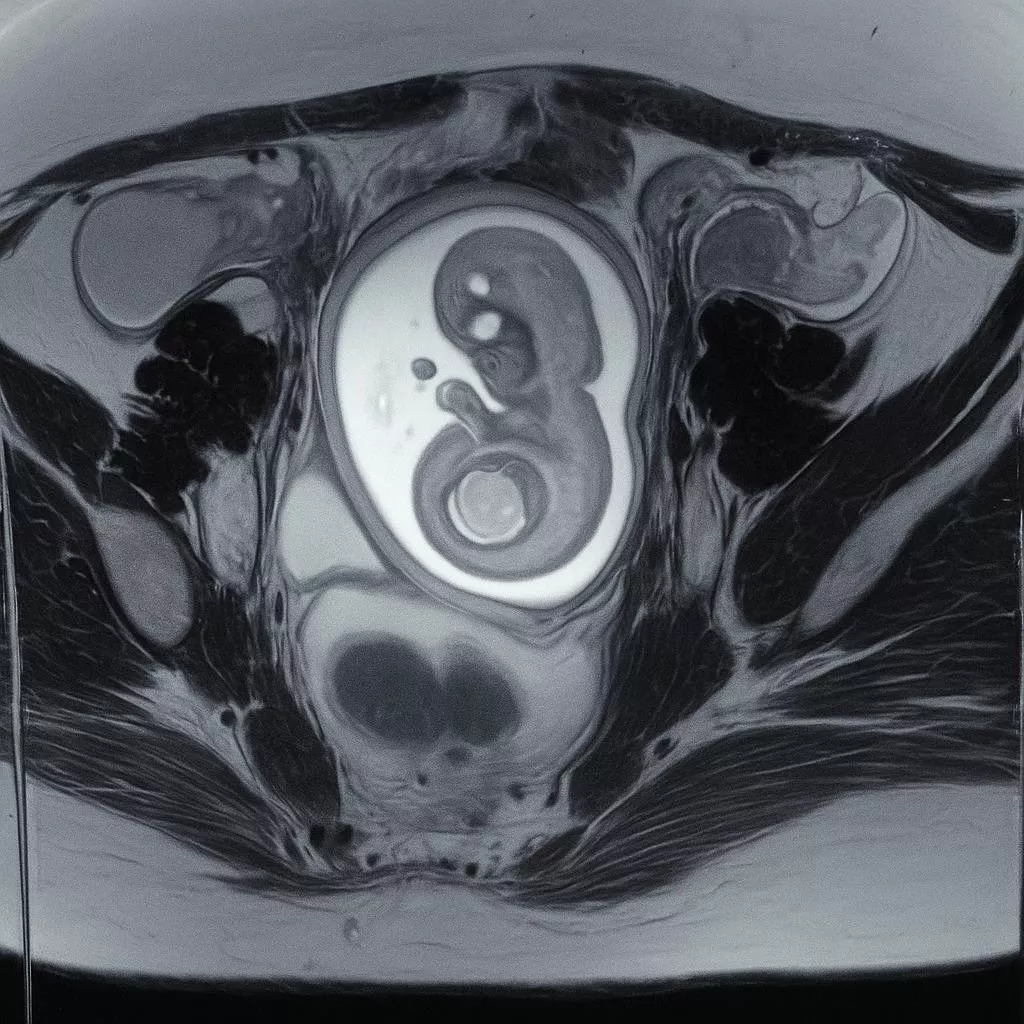

Mammography is an X-Ray examination of breast tissue. The image produced is called mammogram. A mammogram can help detect problems with your breasts, such as cysts or cancer.